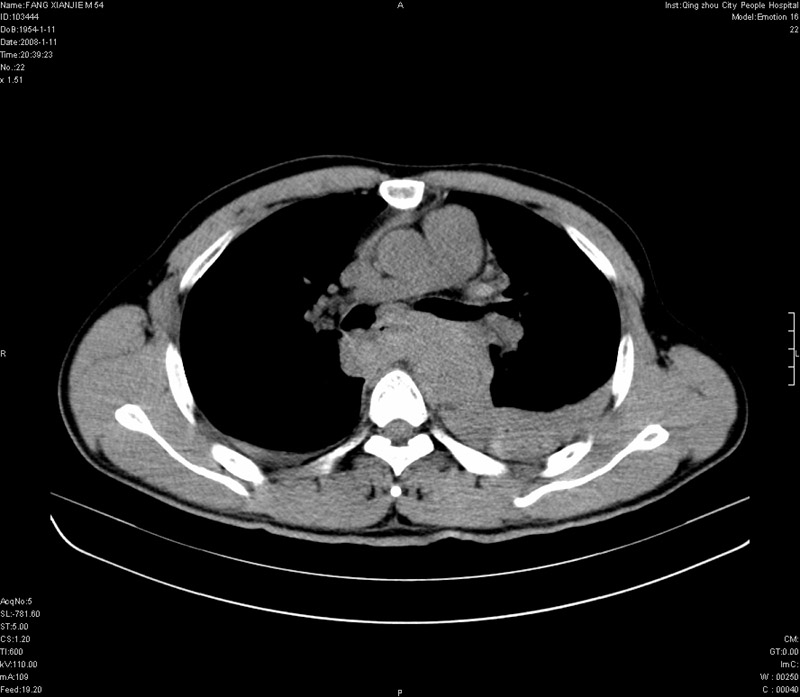

男性,40岁。胸部被车压伤伴胸痛1小时来院就诊。检查:一般情况尚可,血压110/80,胸部及上腹部压痛。结果在三天后公布。骨窗在横断位、冠矢状显示肋骨、胸椎、和胸骨未见骨折征象。

ct11308:胸部外伤1小时(证实病例) (2008-1-13 16:2)结果如下:病人入院后两小时后症状加重,8小时后在征得病人家属同意做了ct增强扫描。如下图。最终临床诊断:外伤性胸主动脉破裂并纵隔内血肿。由于有运动性伪影,胸骨在矢状面重建的图像似有骨折征,这是一种假象,我们称之为“假骨折”,这在多层ct重建中经常性遇到,必要时要结合横断图像鉴别之。现在,病人的一般情况较差,是否要手术家属尚有争议,如果手术修补,难度较大,需要专门预定制作固定支架。

当然,对于该病例,其它非重要的诊断还有:右侧少量气胸;左侧胸腔积液;左侧轻度肺挫裂伤。对于纵隔内血肿,我们曾经遇到过多例,也有怀疑主动脉的破裂,但是,均未得到具体出血部位的明确诊断。